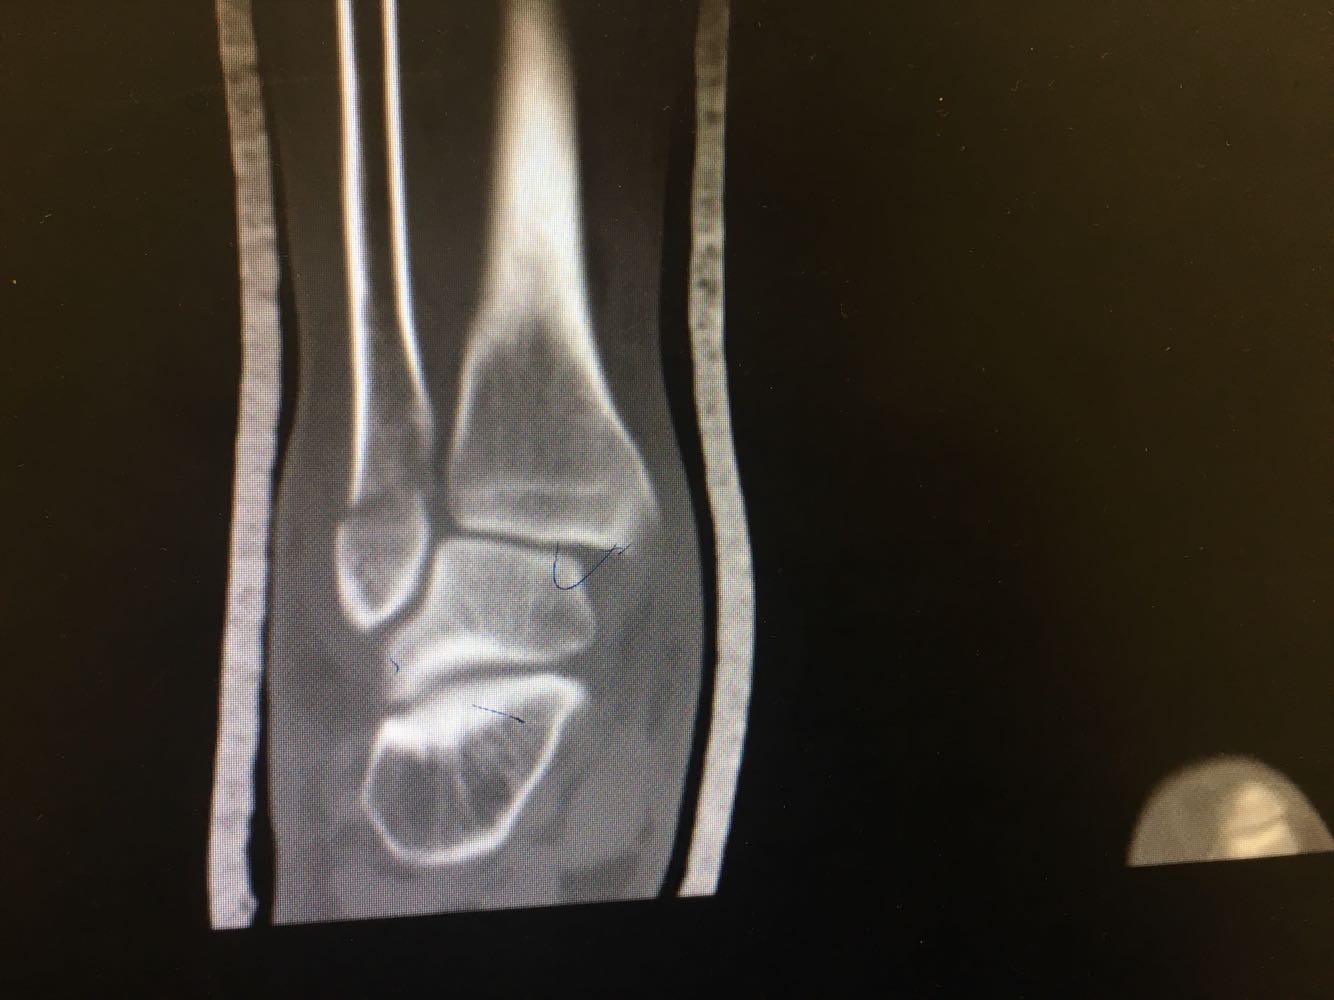

患者,男,54岁。 主诉:外伤致右踝疼痛伴活动受限2天 现病史:患者于2天前不慎扭伤致右踝疼痛,伴活动受限,否认头晕头痛、恶心呕吐等不适,就近医院就诊,查X片示:右踝骨折,予石膏外固定,现为进一步诊治收治入院,发病以来,神清,精神可,胃纳夜眠可,二便无殊,体重无明显变化。

查体:右踝压痛,活动受限,无淤斑淤点,未见皮肤破损,足趾感觉及运动良好。 辅检:右踝部CT

诊断:右侧踝部闭合性骨折 治疗:完善术前检查后行手术内固定